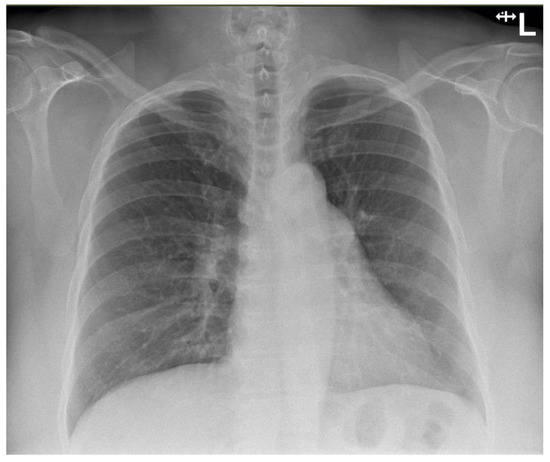

4. Investigations